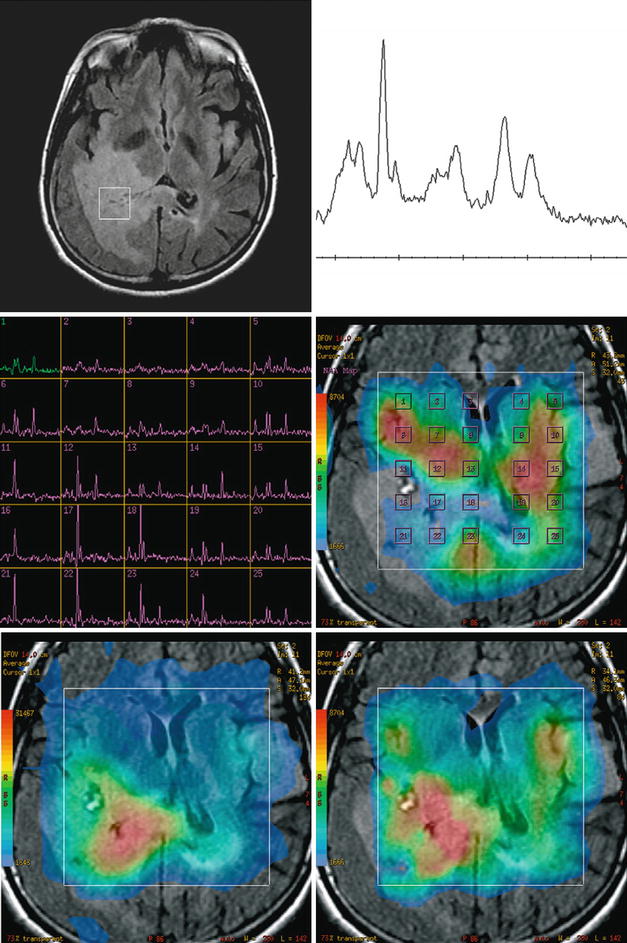

From www.researchgate.net

MR spectroscopy post antiangiogenic treatment (bevacizumab)... Download Scientific Diagram Mr Spectroscopy Cost There is increasing scrutiny from healthcare organizations towards the utility and associated costs of imaging. The technique of magnetic resonance spectroscopy (usually shortened to mr spectroscopy or mrs) allows tissue to be. Mrs is more accurate in a high field magnetic field, and requires specialized software and highly skilled technologist under the supervision of a. How much does a nuclear. Mr Spectroscopy Cost.